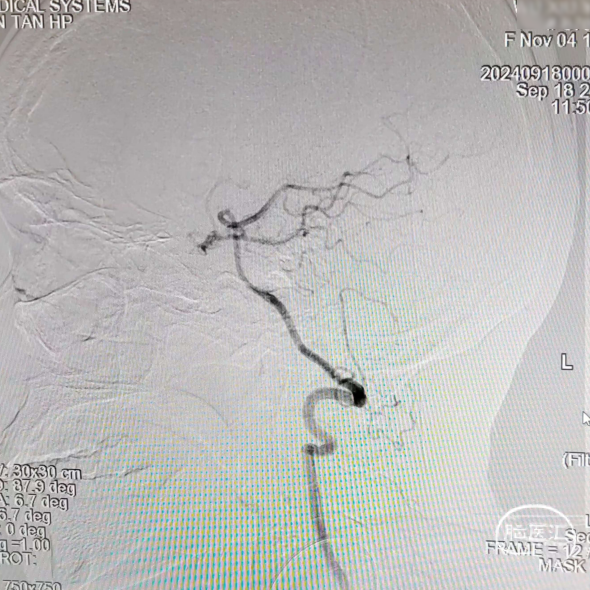

术前造影

RVA正位

RVA侧位

LVA正位

LVA侧位

LCA正位

LCA侧位

沿泥鳅导丝送入5F多功能携带8F导引导管至左侧颈内动脉C1段闭塞处,撤出泥鳅导丝及多功能导管,进行造影。

在路径图下,沿导引导管同轴技术送入微导丝(Command ES 0.014inch 300cm)带Rebar 18微导管至左侧颈内动脉C1段闭塞处,应用微导丝多次尝试成功通过闭塞处,撤出Command交换为Transend微导丝送至大脑中动脉远端。

微导丝、微导管到位后造影,证实微导管位于真腔内。

撤出微导丝,在微导管引导下将5.0*35mm Syphonet®取栓支架送至左侧大脑中动脉M1段,防止血栓逃逸,起到保护作用。

撤出微导管,沿5.0*35mm Syphonet®取栓支架导丝送入2.0*20mm Emerge球囊到达左侧颈内动脉闭塞段远端,充盈球囊至8atm,抽瘪球囊,从远端开始球囊扩张,直至颈内动脉起始处。

造影见左侧颈内动脉再通,恢复血流,前向血流良好,但血管管腔可见血栓。在微导丝及微导管引导下通过8F导引导管送入0.058inch 115cm 中间导管到位后,开始抽吸血栓,未见明显血栓抽出,给予替罗非班(6ml/h)。

造影可见颈内动脉C1段仍有狭窄,退出中间导管,在8F导引导管内沿5.0*35mm Syphonet®取栓支架导丝植入一枚Wallstent支架(9.0*50mm)。

再次造影时发现最狭窄处狭窄改善不满意,再经5.0*35mm Syphonet®取栓支架导丝引导下送入2.5*20mm Emerge球囊,在支架内给予球囊扩张。

最后将8F导引导管撤至左侧颈总动脉,造影可见左侧颈内动脉血流通畅,前向血流III级,远端各分支显影良好。